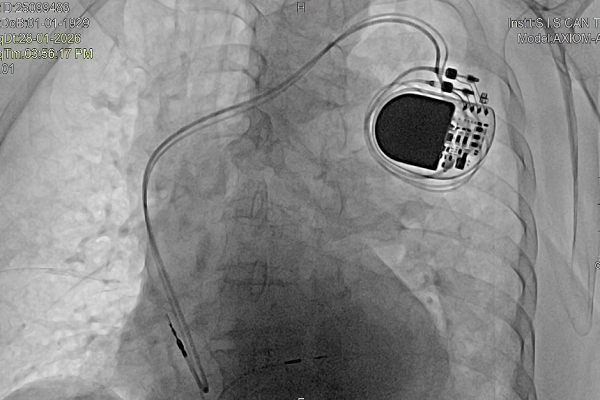

Nhận định về mức độ nguy hiểm của ca bệnh, BSCK2 Nguyễn Mạnh Cường – Phó khoa Nội Tổng hợp, S.I.S Cần Thơ – cho biết tình trạng rối loạn nhịp của bệnh nhân là vô cùng nghiêm trọng, đặc biệt trong bối cảnh tuổi cao, sức yếu. Để ổn định huyết động ban đầu và hỗ trợ nhịp tim, ê-kíp điều trị đã tiến hành đặt máy tạo nhịp tạm thời. Đây là bước đệm quan trọng giúp bệnh nhân đủ điều kiện thực hiện các xét nghiệm chuyên sâu như xét nghiệm máu, chụp X-quang phổi và chụp mạch vành bằng hệ thống DSA.

Quá trình tầm soát cho thấy mạch vành của bệnh nhân hẹp mức độ vừa – tình trạng phù hợp với quy luật lão hóa tự nhiên ở độ tuổi U100 và có thể kiểm soát bằng điều trị nội khoa. Tuy nhiên, vấn đề cốt lõi vẫn nằm ở hệ thống dẫn truyền điện học của tim. Sau khi hội chẩn kỹ lưỡng, các bác sĩ thống nhất phương án điều trị tối ưu là đặt máy tạo nhịp tim vĩnh viễn nhằm duy trì nhịp tim ổn định, bảo đảm cung lượng máu cho toàn cơ thể.

Thay vì áp dụng phương pháp cấy máy tạo nhịp truyền thống, các chuyên gia tại S.I.S Cần Thơ đã lựa chọn kỹ thuật cấy máy tạo nhịp bó nhánh trái. Đây là một trong những kỹ thuật tiên tiến đang được bệnh viện triển khai mạnh mẽ trong những năm gần đây. Tại Việt Nam, số cơ sở y tế có khả năng thực hiện kỹ thuật này vẫn còn hạn chế, chủ yếu tập trung tại các bệnh viện sở hữu trang thiết bị hiện đại và đội ngũ bác sĩ chuyên sâu về điện sinh lý tim.

Theo BSCK2 Nguyễn Mạnh Cường, ưu điểm nổi bật của kỹ thuật cấy máy tạo nhịp bó nhánh trái là giúp nhịp tim được dẫn truyền gần với sinh lý tự nhiên nhất. Bằng cách tác động trực tiếp vào hệ thống dẫn truyền, phương pháp này bảo tồn chức năng co bóp của thất trái, từ đó giảm đáng kể nguy cơ suy tim về lâu dài. Đối với người cao tuổi, đây là lựa chọn tối ưu vì vừa đảm bảo hiệu quả điều trị cao, vừa hạn chế biến chứng.

Ca can thiệp cho cụ N. được ghi nhận là trường hợp bệnh nhân lớn tuổi nhất từng được điều trị bằng kỹ thuật bó nhánh trái tại S.I.S Cần Thơ. Dù phải đối mặt với nhiều thách thức từ tuổi tác và tình trạng bệnh lý phức tạp, ca thủ thuật vẫn diễn ra thuận lợi.